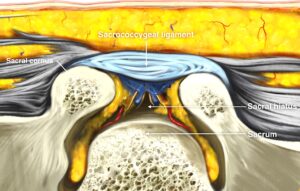

仙骨裂孔硬膜外神経ブロック

腰臀部の痛みや下肢の神経痛が強いときに行う神経ブロック治療です。

主に腰部椎間板ヘルニア・腰部脊柱管狭窄症に対して行います。罹患神経周囲に薬剤が届き神経の炎症や痛みの悪循環をブロックします。数回やっても効果の少ないときは中止します。ブロック後20~30分休んで頂きます。

超音波ガイド下で刺入